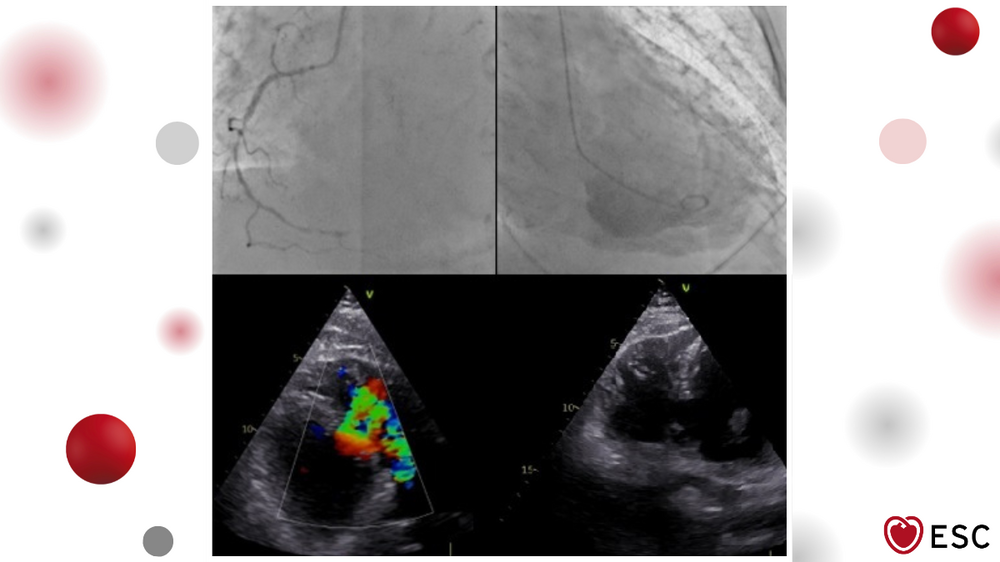

Image of the Week 21 January 2026

The Image of the Week was submitted by Astrid DeClercq from AZ Maria Middelares, Ghent, Belgium